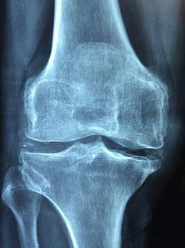

무릎통증 원인 3. 골관절염

골관절염은 노화로 인한 연골의 파괴로 발생하는 질환으로 무릎통증을 일으키는 대표적인 원인 중 하나입니다. 골관절염은 연령이든 성별이든 누구에게나 일어날 수 있으며, 무릎관절의 통증 뿐만 아니라, 염증으로 인한 열감, 붓기 등의 증상을 동반합니다.